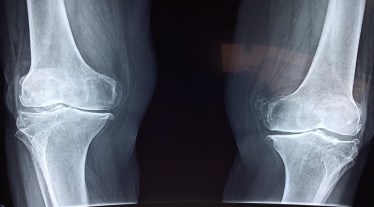

Osteonecrosis is a progressive bone disease that leads to the death of bone tissue due to interrupted blood supply. According to health experts, during the initial stages the patient is asymptomatic, however, as the disease progresses, it affects the structure and eventually the function of the joint. Meanwhile, the advanced stage involves the collapse of the femoral head and arthritis.